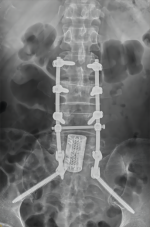

8. 机器人导航辅助下脊柱侧弯矫正技术

脊柱侧弯是一种复杂的脊柱三维畸形,其中以青少年特发性脊柱侧凸最常见。我院在浦口地区率先开展机器人导航辅助下脊柱侧弯矫正术,实现了脊柱侧弯手术准确、微创、智能化的突破,获得了良好的效果。还有老年人退变性侧弯,机器人亦可精准置入困难椎弓根螺钉,误差只有0.3mm。